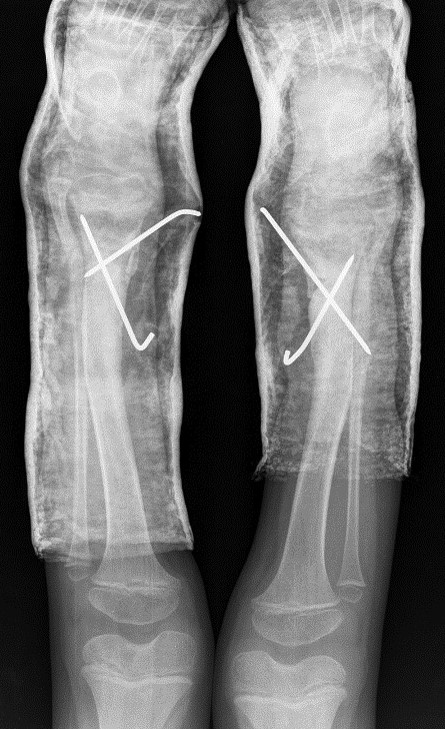

Surgical correction was scheduled. It was performed an opening wedge tibia osteotomy and filled the remaining gap with structural fibular graft. It was fixed with two crossed K-wires and cast immobilization. Both surgeries were performed at the same operative time (Figs 3 and 4).